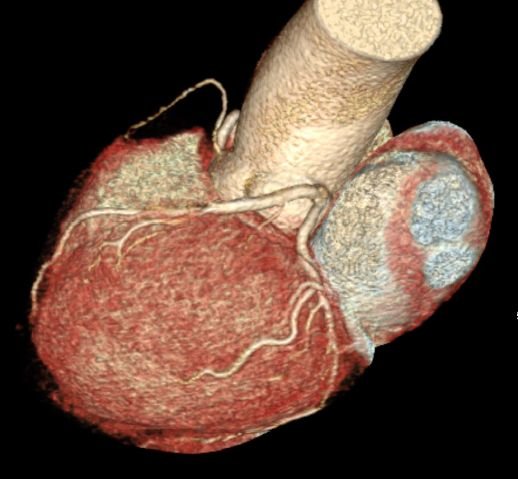

CT Heart

CT Cardiac Anatomy